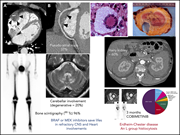

Erdheim-Chester disease

Pericardial localization of Erdheim-Chester disease. Pericardial infiltrate made up of histiocytes positive for CD68 (immunostaining with a KP1 clone). See the review series on rare systemic hematologic disorders in this issue.